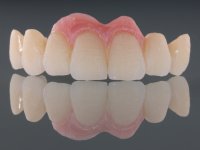

In view of the clinical situation, oral rehabilitation was proposed to improve the aesthetic appearance, but also to solve the lack of posterior teeth, seeking a functional and aesthetic rehabilitation. The plan included replacing the metal-ceramic bridge by a bridge with Zr infrastructure coated with coronary and gingival ceramics. The edentulous area of the first quadrant would be rehabilitated with 2 implants and a bridge of two elements. It was intended with this treatment plan, to recover the vertical dimension of the occlusion and to reshape the dental anatomy, thus creating a more natural aesthetic appearance.

Alginate impressions were made at both arches arcades, accompanied by intermaxillary registration relations and collecting information with facial bow facial bow. In the laboratory, a provisional bridge with 13 elements in autopolymerizable acrylic was built, in which a metallic reinforcement was included. Teeth 1.7 / 1.4 / 1.3 / 2.2 / 2.3 / 2.4 and 2.6 were used as pillars. The metal-ceramic bridge was removed after performing longitudinal cuts with diamond burs. The dental abutments were reprepared and the temporary bridge was relined in the mouth with self-curing acrylic. After confection of the provisional bridge, a gingival epithesis was made using composite resin with gingival tonality in order to function as a mock-up, which allowed the patient to preview the possibility of using gingiva shade ceramics in the final work. This option was approved by the patient. Subsequently, the placement of two implants in the first quadrant was planned and executed. The provisional monoblock was removed for placement of the implants, and after surgery was again cemented provisionally. After the osseointegration period, the impressions were made to the maxilla. In the anterior zone, impregnated gingival retraction cords were used, and in the posterior areas, kaolin paste was used. Implant printing utilized the open tray technique. The printing material used was soft and regular putty addition silicone, both fast-setting. In the laboratory, the model of provisional restorations and the gingiva epithesis mock-up served as orientation for waxing the infrastructure. The plaster work model and the waxing of the infrastructure were placed in a laboratory scanner and yielded a digital work model, in which the scanning of the waxed infrastructure was superimposed. This overlay facilitated the CAD design of the Zr infrastructure. Subsequently, the CAD drawing for a CAM milling process provided the Zr pieces. The infrastructure was pigmented with a pinkish coloration, which favors the subsequent placement of gum shade ceramic. During the modeling of the infrastructure, the need to increase the occlusal wear on tooth 1.4 was detected. This was done in the real working model cast and an acrylic wear control guide was created, which accompanied the proof of the infrastructures. Corrective wear and Zr parts test were performed in mouth. During the test, the color choice of the gum shade ceramic was reassessed. The treatment was finished in the laboratory, and after approval by the patient, was definitively placed in the mouth.